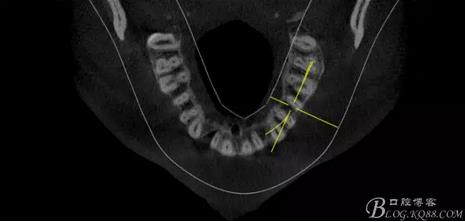

(1) 檢查:12唇側(cè)牙齦可見竇道,牙體顏色較鄰牙暗,無光澤,形態(tài)完整無缺損,唇側(cè)及近遠中向未提及牙周袋。腭側(cè)齦緣輕度紅腫,舌側(cè)窩可探及裂溝,可見浸墨狀痕跡,沿裂溝舌側(cè)探診牙周袋深大于11mm,除患牙外全口牙周狀況良好,為探及牙周袋,牙齦色粉紅。邊緣菲薄,質(zhì)地堅韌。12冷熱診無反應,叩診(+-),無明顯松動,無咬合創(chuàng)傷。12根尖x線片示,根管中三分之一中可見一斜向線樣透射影像根尖區(qū)及遠中根三分之一可見低密度透射暗影,錐形束CT示12根尖區(qū)唇腭向骨吸收已穿通,根面溝達根中三分之一卷曲分出另一牙根,再未見其他明顯的根管系統(tǒng)。